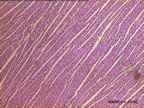

Kalp kası yapı bakımından çizgili kasa benzese de çalışması çizgili kas gibi isteğimizle değil, istemsiz çalışır. Kasın çalışması kontrolü sinir sistemiyle olmaktadır. Sinirlerdeki bozulma, kasta felce yol açar. Kas dokusu, vücudun hareketini sağladığı için diğer dokulara oranla daha fazla oksijene ve enerjiye ihtiyaç duyar. Kalp kasında çekirdekler ortadadır.Kas lifleri iskelet kasındaki gibi düz lifler seklindedir. Fakat, bazen çatallanma yapar.